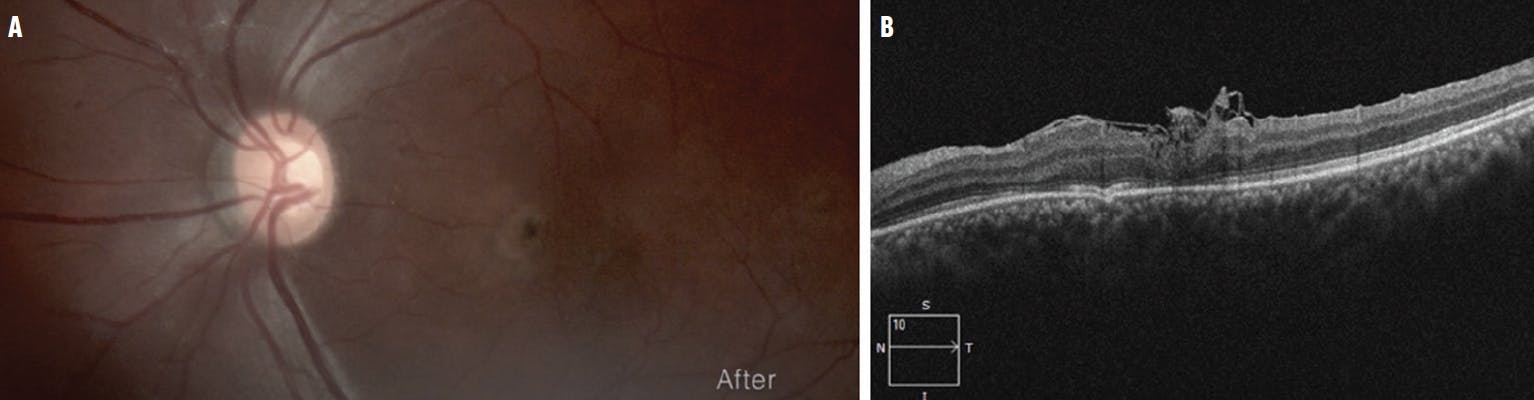

A 36-year-old woman presented with TMH in the left eye following a car accident. Initial treatment included vitrectomy with ILM peeling 1 month after the event; however, the hole closure was incomplete with poor anatomic and functional outcomes (Figure 1A). Her initial VA was 20/100, and a full-thickness MH (FTMH) with elevated edges and intraretinal cysts was documented via OCT, with a basal diameter of 1,152 µm (Figure 1B).

<p>Figure 1. The FTMH is still evident after the first procedure with vitrectomy and ILM peeling (A). OCT shows the FTMH, elevated edges, and intraretinal cysts (B).</p>

Figure 1. The FTMH is still evident after the first procedure with vitrectomy and ILM peeling (A). OCT shows the FTMH, elevated edges, and intraretinal cysts (B).